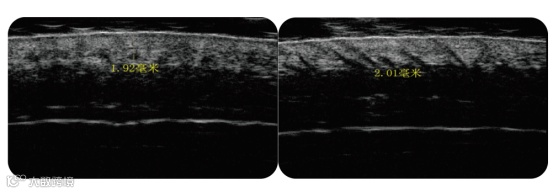

头皮衰老过程中,胶原蛋白流失,纤维碎片化,功能成分减少,导致成纤维细胞分泌能力降低,最终导致头皮变薄,头皮松弛。

一个强韧的头皮会令头发的生长更健康。促进胶原蛋白及弹性纤维再生,实现头皮增厚,让头发得以在有厚度的头皮上更深层的扎根。